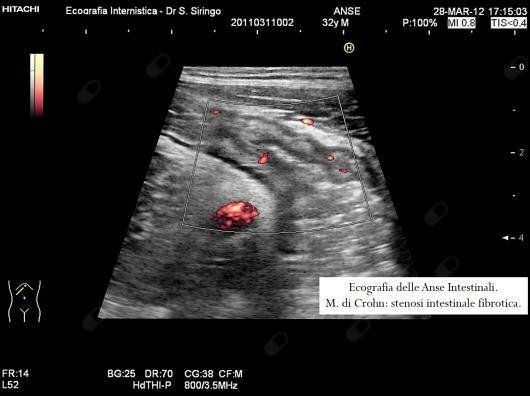

E’ una metodica di primo livello da impiegare nello studio dei disturbi addominali. In particolare, insieme ad alcuni specifici esami di laboratorio, permette un’agevole diagnosi differenziale tra colon irritabile e malattie infiammatorie dell’intestino quali la m. di Crohn e la colite ulcerosa. Inoltre, nel sospetto di m. di Crohn, consente di orientare rapidamente la diagnosi permettendo di rilevare l’ispessimento delle pareti del piccolo intestino e del colon che contraddistingue questa malattia.

Nella m. di Crohn, dopo la diagnosi, è un utilissimo mezzo per seguirne l’evoluzione, la risposta alla terapia e rilevare le possibili complicazioni quali ascessi o restringimenti dell’intestino.